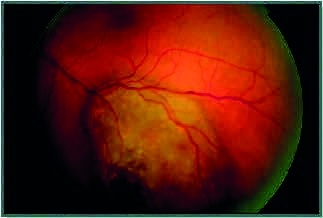

Darunter werden Erkrankungen des Glaskörpers (Vitreus), der Netzhaut (Retina) und Aderhaut und Lederhaut (Uvea) subsummiert. Oftmals korrelieren geklagte Beschwerden und Krankheitswert nicht, wie z. B. bei Glaskörpertrübungen. Dabei zirkulieren Teile des Glaskörpergerüsts oder einzelne Zellen im Glaskörper und erzeugen sogenannte „Fliegende Mücken“ (mouches volantes). Der Patient nimmt dieses als zum Teil sehr störend war, es ist aber meist völlig ungefährlich. Andererseits müssen akute Symptome aktuell abgeklärt werden, da es bei einer akuten Abhebung der Glaskörpergrenzmembran bei der Verflüssigung des Glaskörpers alters- oder myopiebedingt zu Netzhauteinrissen kommen kann, die bei nicht umgehender Laserbehandlung zur Netzhautablösung führen kann. Im Bundeswehrkrankenhaus Ulm steht ein Zentrum der Netzhaut- und Glaskörperchirurgie zur Verfügung. Falls die alleinige Laserbehandlung nicht ausreicht, kommen die sogenannte Pars Plana Vitrektomie, Endolaser oder Eingabe von medizinischen Gasen oder Ölen zum Einsatz. In den letzten Jahren sind auch große Fortschritte bei der Behandlung von zentralen Netzhauterkrankungen (Makuladegeneration, Venenverschlusskrankheit, diabetisches Makulaödem) erzielt worden durch Eingabe von Anti-VEGF (Anti-Wachstumsfaktoren) oder cortisonhaltigen Medikamenten mittels IVOM (intravitreale operative Medikamenteneingabe).

Zur Diagnostik bei der Netzhautuntersuchung im Rahmen einer Vorsorge stehen ebenfalls moderne Geräte zur Verfügung (OCT-scan Optical Coherence Tomographie kam im Jahre 2017 ca. 1.200 mal zum Einsatz, ebenso Funduskamera und Ultraschall). Nach der Pupillenerweiterung können Untersuchungen der Netzhaut erfolgen bei Diabetes, Hypertonie und zum Ausschluss von Sehnervenerkrankungen (siehe Glaukom) oder bei z. B. Hirntumoren (Stauungspapille). Bei Erkrankungen des ZNS, wie z. B. Multiple Sklerose, wird die Untersuchung der Nervenfaserschicht vorgenommen. Beurteilt werden kann dann auch die periphere Netzhaut, um Netzhautlöcher und Tumoren (bei Kindern z. B. das Retinoblastom, bei Erwachsenen das Aderhautmelanom mit einer jährlichen Häufigkeit von 5 Erkrankungen pro 1 Million) oder Metastasen an der Netzhaut bei z. B. Mammakarzinom auszuschließen.